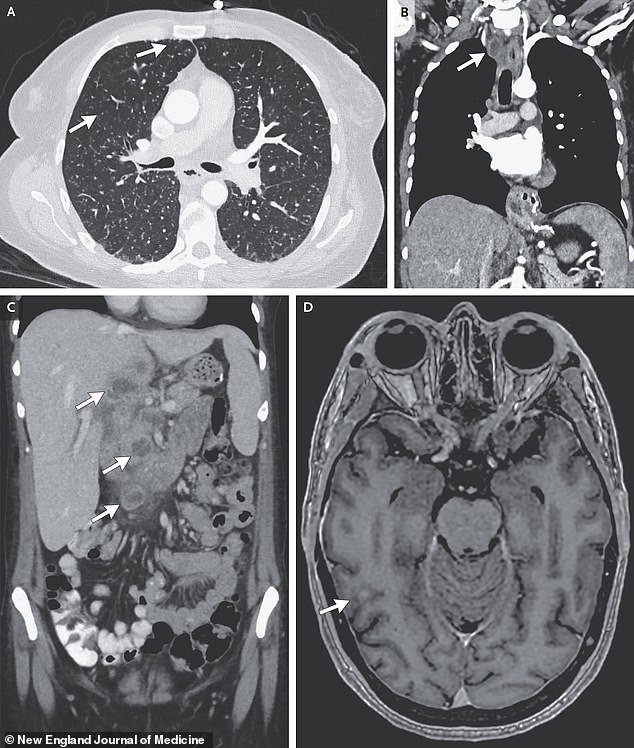

X-ray scans showed several small nodules spread across the woman’s lungs, a sign of bacteria. In additional scans, doctors found the lesions in the liver, lymph nodes, pancreas and brain.

The above scans show nodules in several of the woman’s organs. Image A is a scan of her lungs, with arrows pointing toward the nodules. Image B shows an arrow pointing toward an enlarged lymph node. Image C shows arrows drawing attention to nodules in the liver and head of the pancreas, and Image D shows a nodule in the woman’s brain